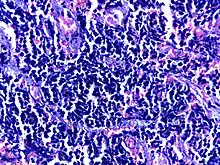

![]() | Diffuse B-cell lymphoma | Lymph node FNA specimen showing diffuse large B cell lymphoma. | Category: Histopathology of diffuse large B cell lymphoma | Diffuse large B-cell lymphoma |